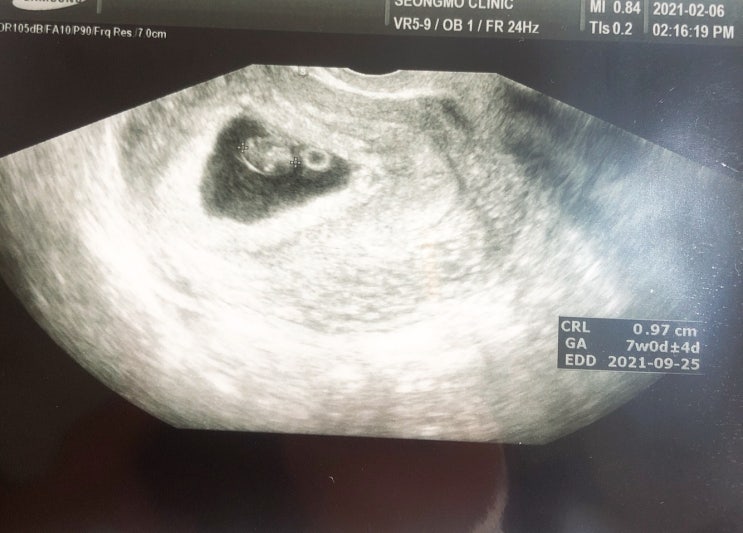

임신 초기 입덧 극복하기

#임신초기입덧 #입덧극복 #입덧완화음식 #사람살려 올해 1월 찾아온 호박이 올초 회사 프로젝트가 너무너무...